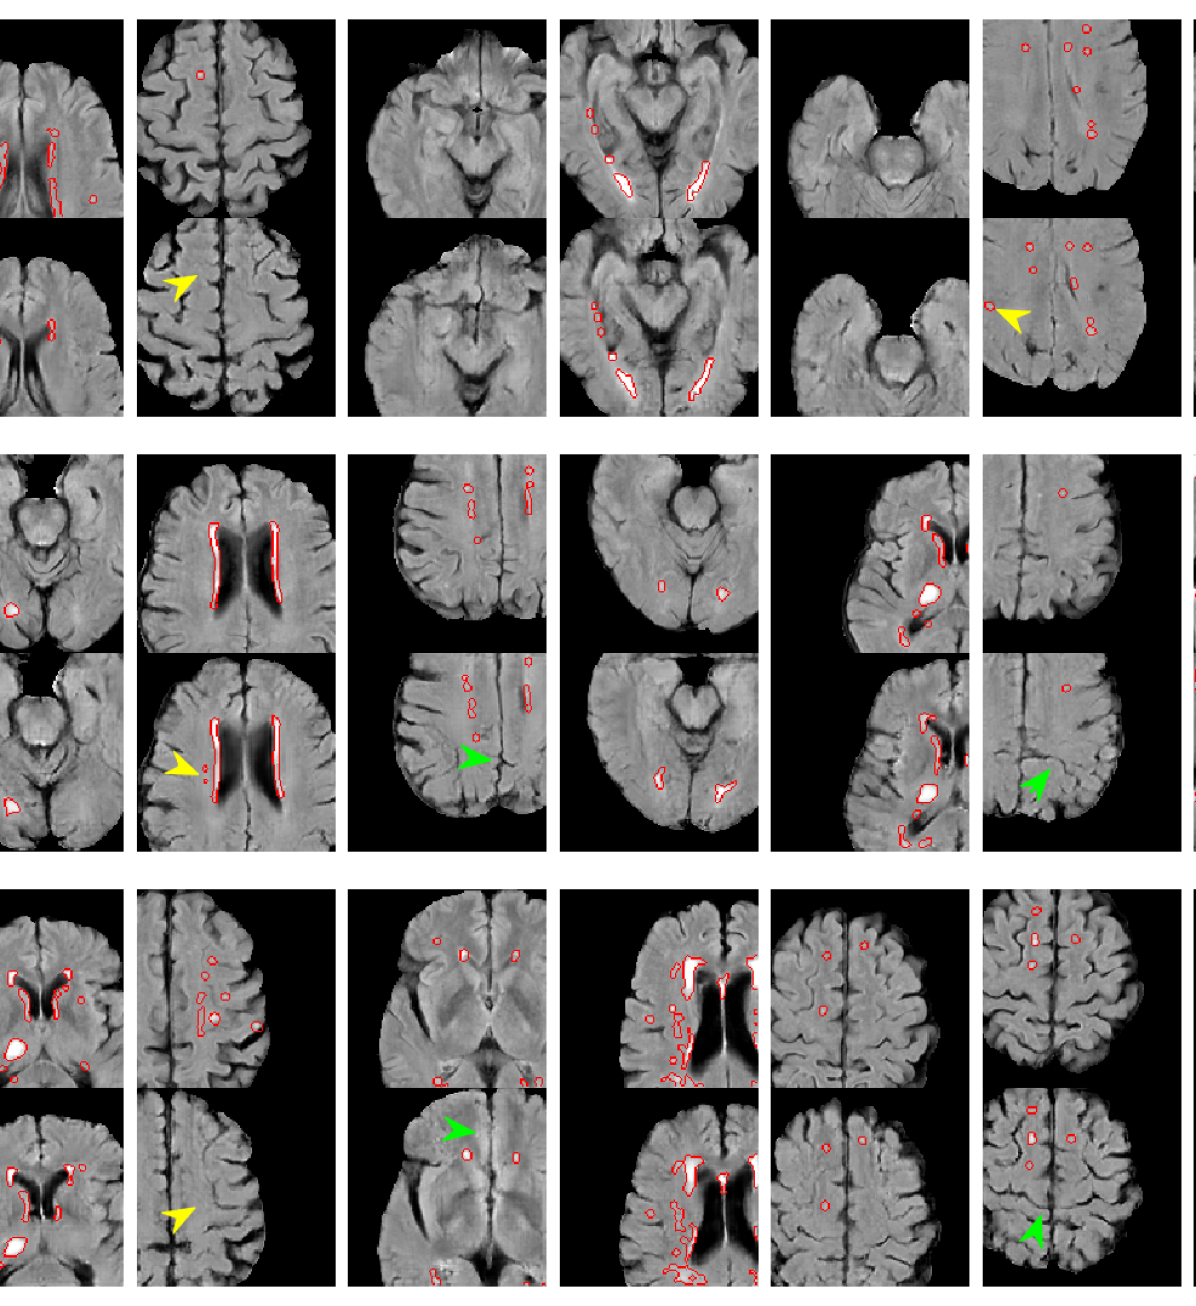

As well as the quantitative segmentation results, the generated MR images were also compared to their nearest neighbour in the training set to elucidate what extra information GAN augmentation provides. These images, a subset of which are shown in Figure 3, were examined looking for cases where: lesions were duplicated on different anatomy; lesions were changed whilst anatomy stays the same; the nearest neighbour is substantially different. The latter indicates the GAN has learned a smooth manifold leading to potentially novel anatomy.

Refer to caption

(a) 5 training images

(b) 25 training images

(c) 50 training images

Figure 3: Synthetic images (top of pair) with their nearest neighbours in the training set (bottom of pair) from GANs trained on patches from 5, 25 and 50 real MR images. Some local signs of successful augmentation are indicated using green (same lesions, different anatomy) and yellow (same anatomy, different lesions) arrows, and novel images (new anatomy and lesions) are shown with blue dots.

Figure 3 provides an interesting insight into what additional information is being provided by GAN augmentation. In the case of 5 training images, it is clear that each generated image is based heavily on an image from the training set. This is unsurprising as there are very few images to train on, and little variation which can be learned. However, there are subtle differences present in the majority of synthetic images. There are cases where lesions present in the real image are not reproduced in the synthetic image, as well as cases where the shape and number of lesions present in the synthetic image differ from those in the real image. Both of these effects can be extremely valuable to prevent overfitting when training a model - the former decoupling the presence of lesions from the surrounding anatomy, and the latter providing more variety of pathology. When the number of training images increases to 25, we begin to see cases where there are no close matches in the training set, in addition to the cases of differing anatomy and pathology seen previously. This trend gets even stronger in Figure 3 where all 50 training images are used. There are often substantial differences between the synthetic images and their closest real image, suggesting that the GAN has learned to produce data substantially beyond what was provided to it. We also observe that these modifications appear reasonable in all cases, with no obvious unrealistic lesions or anatomy being synthesised.